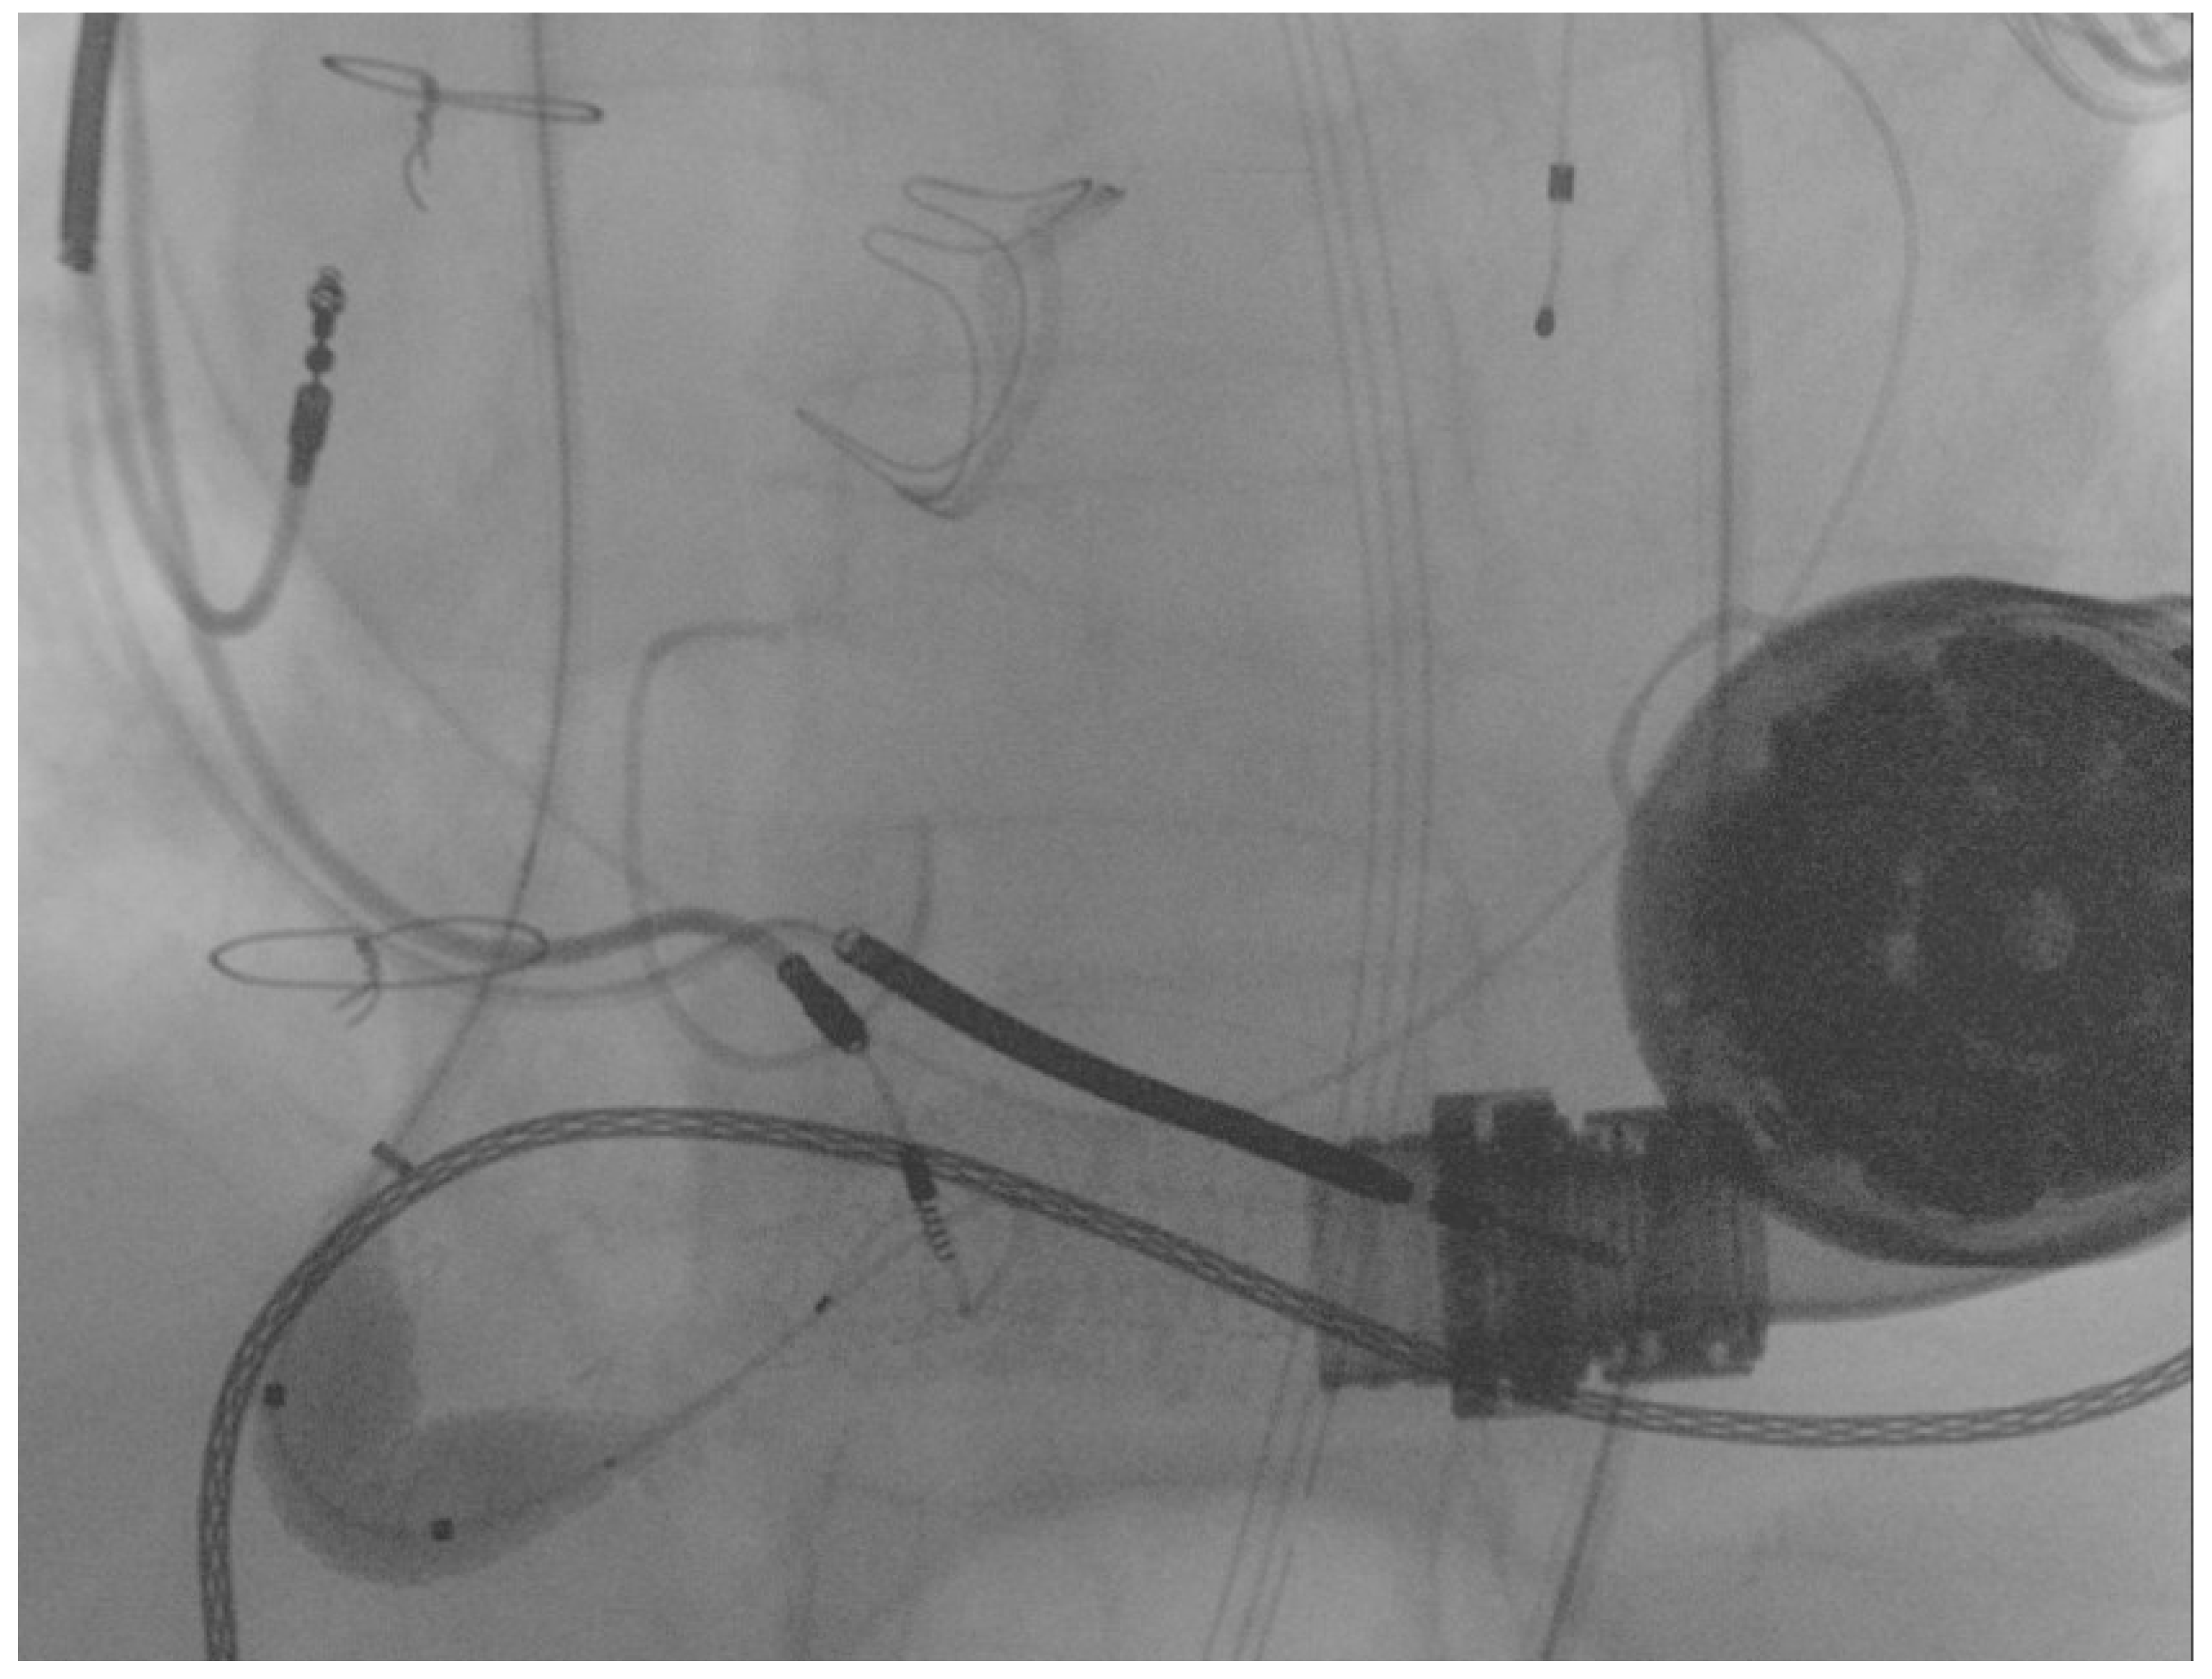

Final angiography showed complete flow restoration and the optimal patency of the stent previously implanted in the proximal segment of the graft 12 months before, as shown in Figure 5.

Figure 5.

Final result following the percutaneous intervention.